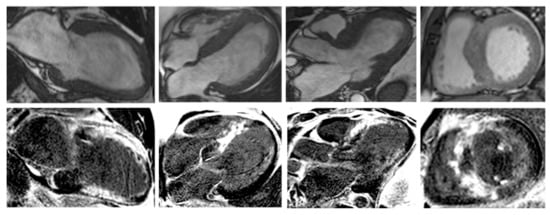

Nonetheless, due to increased temporal resolution, ability to comprehensively evaluate all heart structures and capacity to characterize myocardial tissue and unravel fibrosis, CMR has currently became the gold-standard imaging tool for diagnosing and assessing patients with HCM. CMR is able to accurately quantify heart chambers’ volumes and dimensions and also both LV and right ventricle (RV) systolic functions. Moreover, CMR is the only large-scale available noninvasive imaging tool capable of tissue characterization. This aspect has a tremendous role in patients with HCM since it can identify and accurately quantify both myocardial replacement and diffuse fibrosis and it can also exclude other infiltrative cardiomyopathies such as amyloidosis [27]. CMR summarized in Table 1. Specific cases of HCM assessed by CMR are presented in Figure 2, Figure 3 and Figure 4.

Figure 2. Contrast-enhanced CMR in a 50-year-old male patient with hypertrophic cardiomyopathy (from the own collection of the authors). (Upper row): b-SSFP cine images in two chambers, four chambers, short axis and three chambers, respectively. There is asymmetrical LV hypertrophy, with a maximum thickness of 20 mm at the basal anterior wall. The LV is not dilated and the LVEF is within normal limits (59%). There is systolic anterior motion of the mitral valve, resulting in acceleration of the systolic flow in the LV outflow tract. (Lower row): LGE imaging shows patchy myocardial fibrosis of the hypertrophied segments. Abbreviations: b-SSFP, balanced steady-state free precession; CMR, cardiac magnetic resonance imaging; LVEF, left ventricle ejection fraction; LGE, late gadolinium enhancement; LV, left ventricle.

Figure 3. Contrast-enhanced cardiovascular magnetic resonance imaging in a 32-year-old male patient with a history of hypertrophic cardiomyopathy due to a pathogenic mutation in MYBPC3 gene (c.772G>A) (from the own collection of the authors). The current findings are compatible with a phenotype of burn-out HCM. (Upper row): b-SSFP cine images in two, four and three chambers, and short axis, respectively. The LV is severely dilated (166 mL/m2) with severe systolic dysfunction (LVEF 22%). Currently, there is no LV outflow tract obstruction, although an obstructive phenotype was diagnosed 10 years before. (Lower row): LGE imaging shows extensive heterogeneous replacement myocardial fibrosis at the level of the interventricular septum, anterior and inferior LV walls, respectively. Also note the fibrosis of the papillary mitral muscles. Abbreviations: b-SSFP, balanced steady-state free precession; CMR, cardiac magnetic resonance imaging; LVEF, left ventricle ejection fraction; LGE, late gadolinium enhancement; LV, left ventricle.

Figure 4. Contrast-enhanced CMR in a 50-year-old female patient with a history of hypertrophic cardiomyopathy with LV apical aneurysm (from the own collection of the authors). (Upper row): b-SSFP cine images in four, three and two chambers, and short axis, respectively. The LV is dilated (110 mL/m2) with severely impaired systolic function (LVEF 25%). There is asymmetrical LV hypertrophy with a maximum wall thickness of 28 mm at the level of the interventricular septum. Note the large apical aneurysm with a maximum diameter of 40 mm and thin walls. (Lower row): LGE imaging shows transmural fibrosis of the LV apical aneurysm and a small focal intramyocardial scar at the level of the basal infero-lateral wall. The total percent of fibrosis is 16% of the LV myocardium. No thrombus is seen inside the apical aneurysm. Abbreviations: b-SSFP, balanced steady-state free precession; CMR, cardiac magnetic resonance imaging; LVEF, left ventricle ejection fraction; LGE, late gadolinium enhancement; LV, left ventricle.